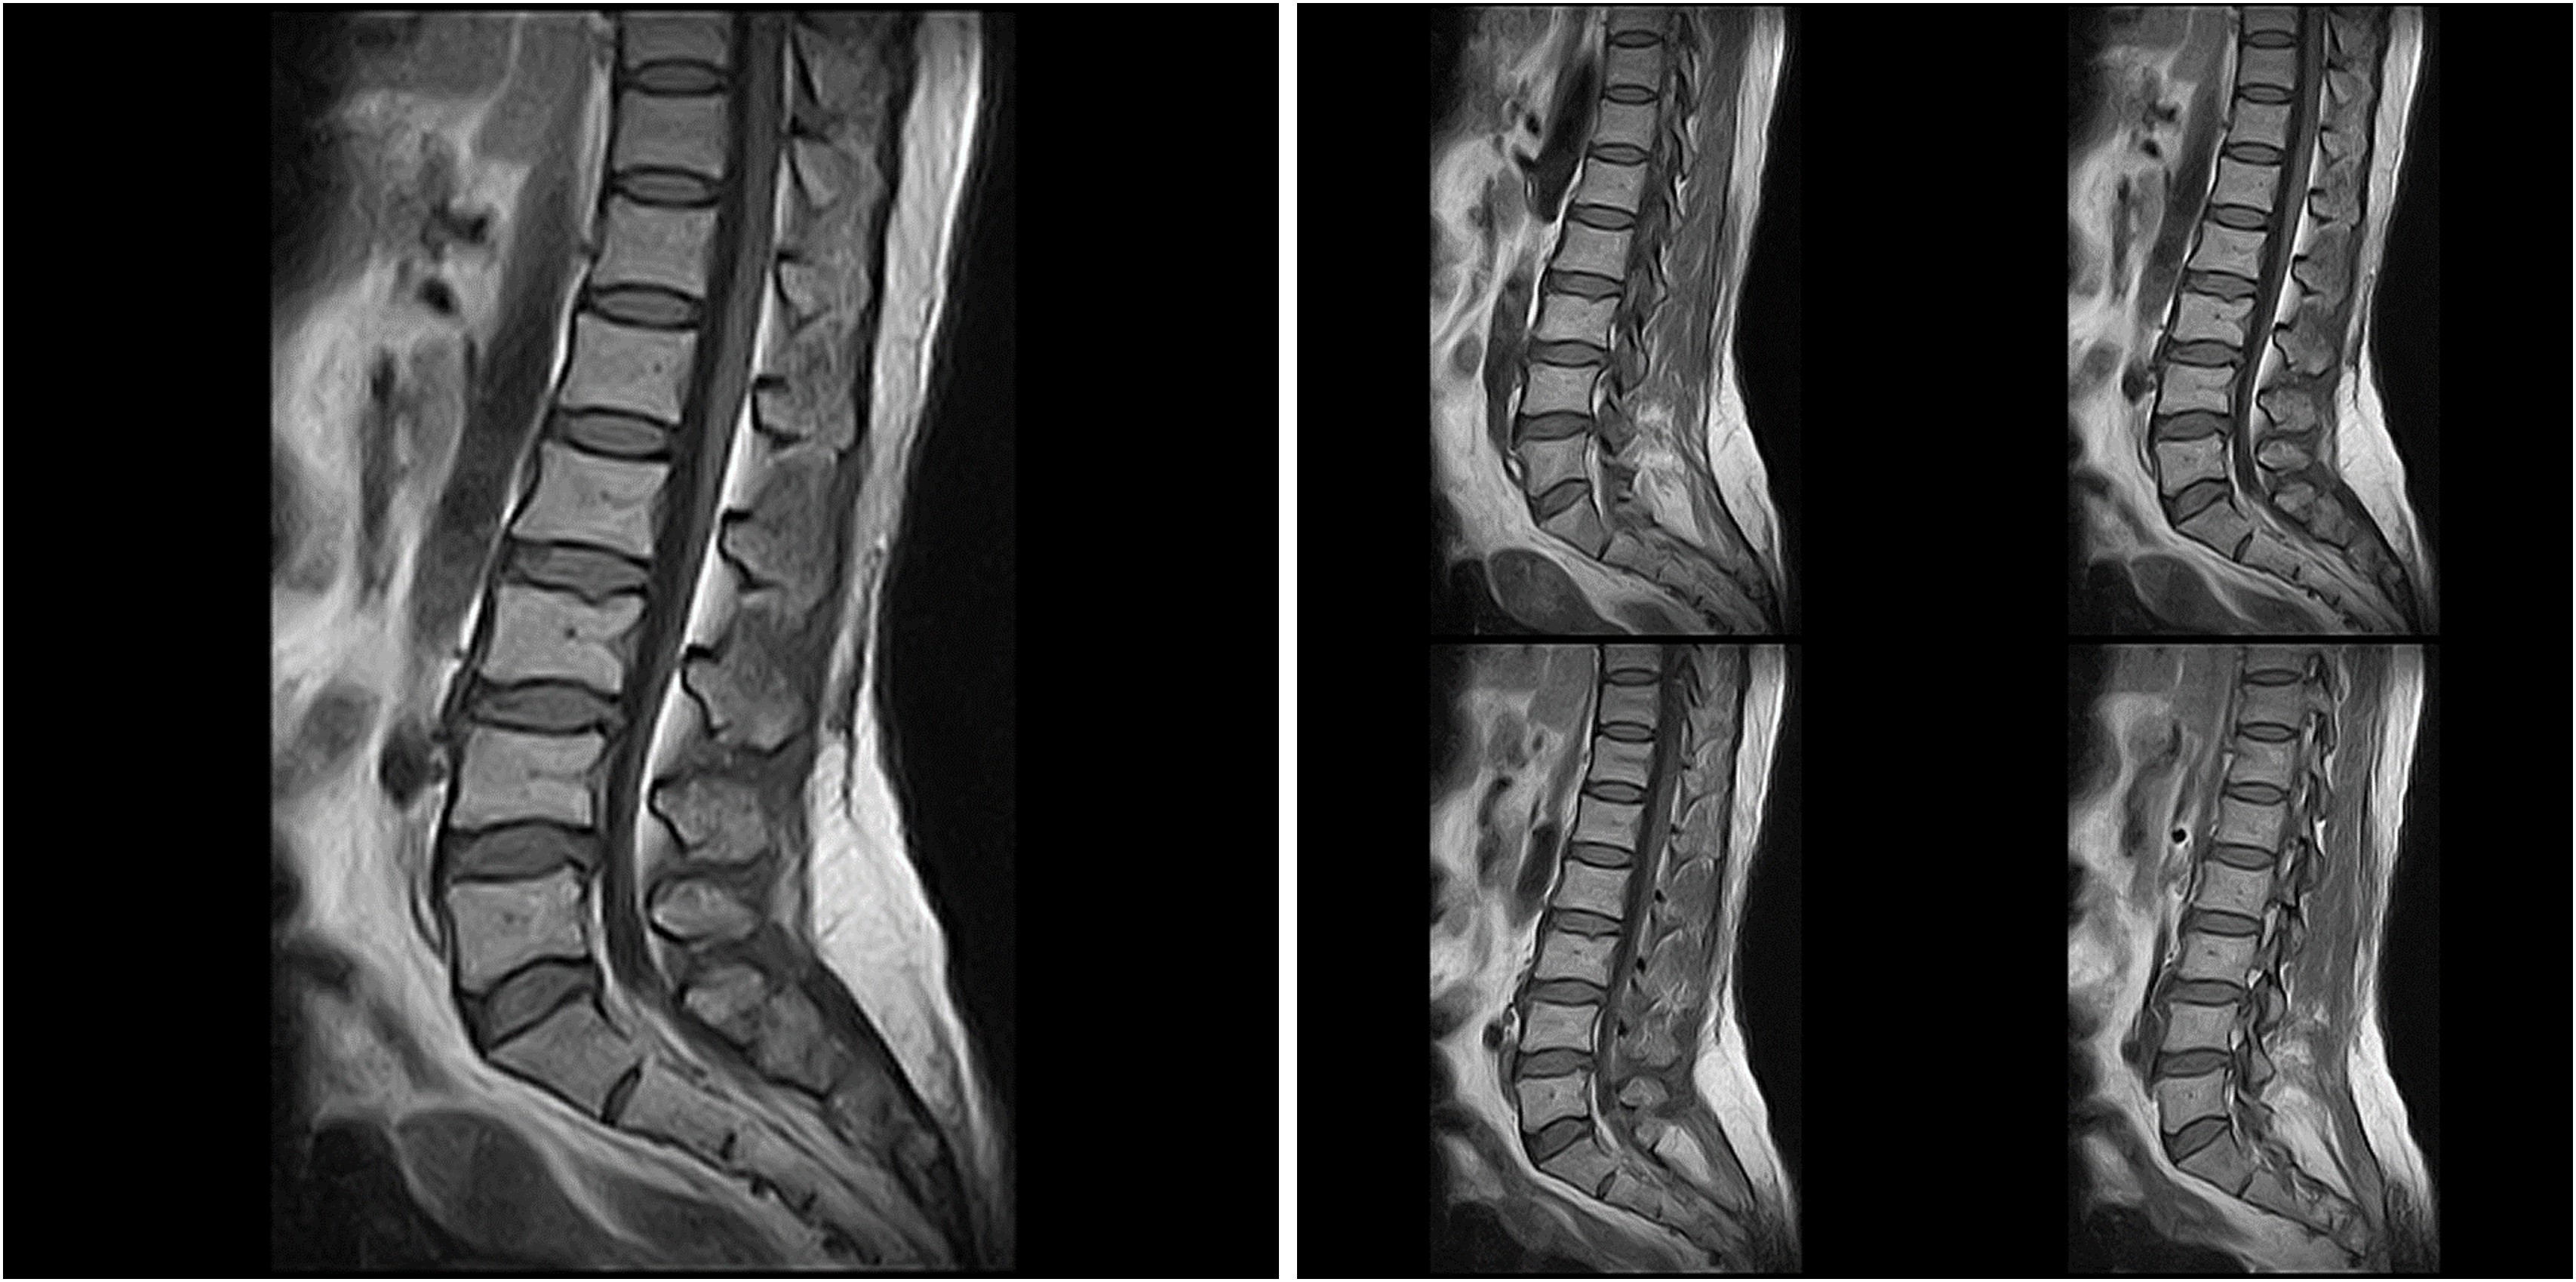

Hình ảnh lâm sàng

Giải pháp lâm sàng ấn tượng